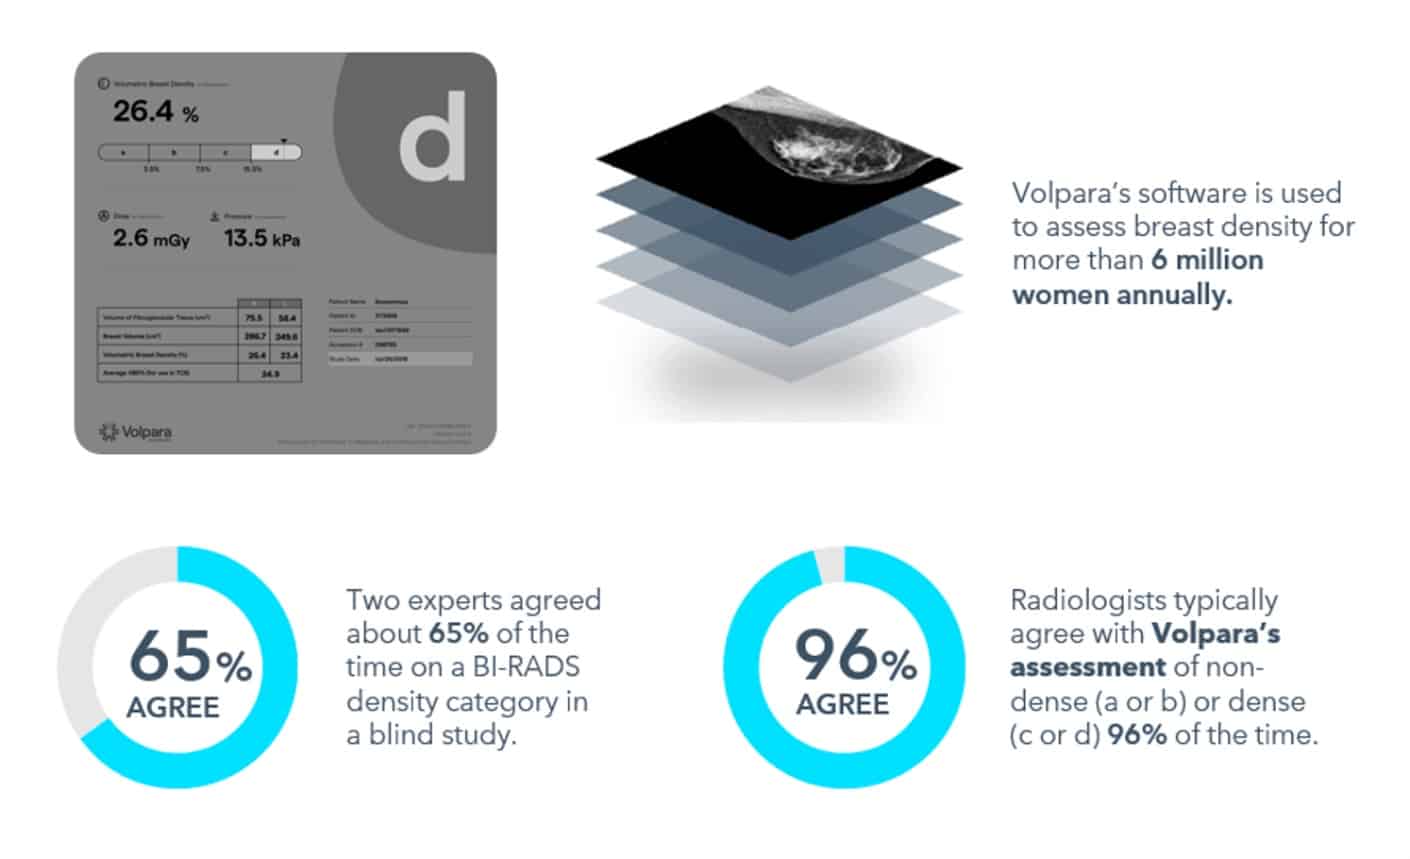

96%* of radiologists agree with Volpara’s assessment of non-dense or dense.

*Data on company file. Analysis from 36,642 cases across four clinics.

Volpara’s FDA-cleared TruDensity™ algorithm powers Scorecard, a breast density assessment software that delivers consistent, volumetric insights. It provides clinicians with consistent, objective data to support earlier cancer detection and supplemental imaging recommendations.

Scorecard is a trusted standard for breast density analysis, used in over 4,800 hospitals and backed by 400+ studies.